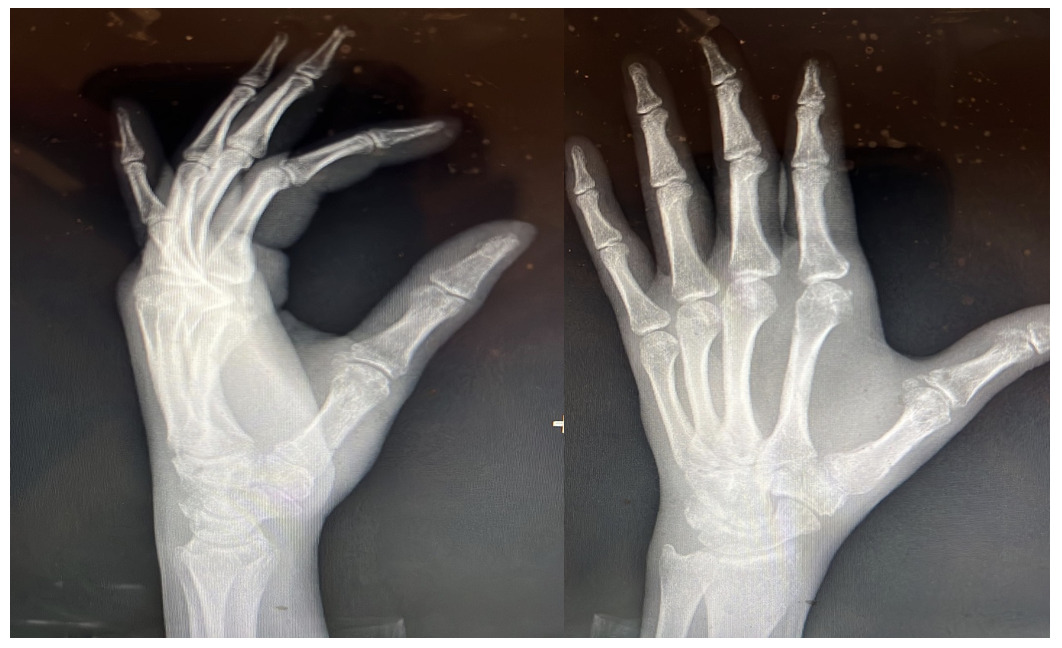

Multiple 1.1 joysticks were used to obtain a near anatomical closed reduction. Then, multiple K-wires size 1.6 and 1.1 were used to secure and fix the trapezium fracture as well as the carpometacarpal dislocation through a wire spanning the thumb metacarpal bone and the trapezium, as well as another wire spanning the thumb and the index metacarpal bones as an added measure of safety to avoid a recurrent dislocation. Closed reduction of the Bennett fracture using a 1.1 K-wire was attempted with acceptable reduction obtained. Fluoroscopic images were satisfactory in multiple planes (Fig.2). Relaxing incisions were done around the K-wires and the pins were cut close to the skin and bent. A sterile dressing was applied followed by a combined sugar-tong and thumb spica splint. The patient’s arm was placed in an arm sling. The splint and pins were removed after 4 weeks.

Repeat X rays showed good alignment and healing in progress (Fig.3) and physical therapy was started. The patient had gradual improvement in his wrist and thumb ROM with the help of physical therapy.